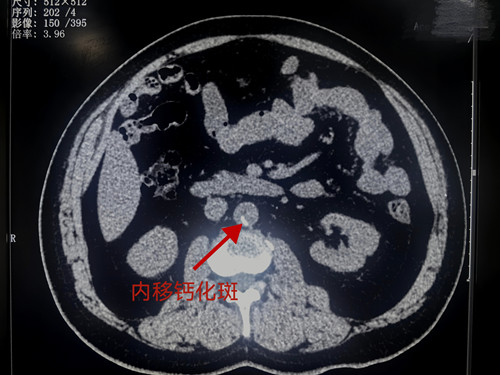

放射科戴炎栋副主任医师在阅片时,敏锐地捕捉到了一个极易被忽略的细节——患者腹主动脉存在小片钙化斑内移,同时伴随髂动脉周围出血迹象。“这个信号不寻常,必须高度警惕!”凭借多年临床经验,戴炎栋立刻联想到凶险的夹层动脉瘤。要知道,主动脉夹层被称为“伟大的模仿者”,症状常与胃病、心梗等混淆,且CT平扫表现隐蔽,漏诊率极高,未经治疗的患者48小时内死亡率高达50%,每小时死亡风险递增1%-2%,堪称“沉默的死神”。

“主动脉夹层的早期诊断是救治成功的关键,而CT平扫的隐蔽性给诊断带来了极大挑战。”戴炎栋医生介绍,常规CT平扫下,主动脉夹层可能仅表现为动脉增粗、钙化斑内移等不典型迹象,如同本次患者仅出现小片钙化斑内移,若稍不留意就可能漏诊,进而延误治疗时机。而胸腹主动脉CTA检查能清晰显示典型的“双腔征”,精准勾勒病变范围和累及部位,为疾病分型、手术方案制定提供可靠依据,其诊断灵敏度和准确率远高于常规CT平扫。